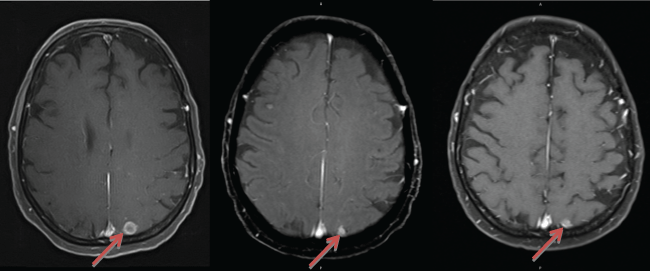

An MRI scan of her brain in September 2013 demonstrated overall improvement and response to radiation, with smaller parietal (1.1 cm), basal ganglia (0.9 cm), and cerebellar (0.7 cm) lesions. PET scan on October 30th showed mixed extracranial response without any uptake in the mediastinum but with new FDG-avidity in a level IV left cervical lymph node (max SUV 2.9 g/mL), as well as increased radiotracer uptake in the distal left femur. She had associated pain in her left femur, and received empiric palliative radiation to this area (18 Gy). Brain MRI on December 27th showed a stable parietal lesion (1.1 cm); however, the basal ganglia (1.2 cm) and cerebellar (1.1 cm) lesions had enlarged, and there were multiple new smaller lesions (Figure 1A). Her lesions were still asymptomatic. CT imaging on December 30th also showed progression of disease, with bony metastases in the left 10th rib and left iliac wing.

Figure 1: Brain MRI images showing regression and stabilization of parietal lesion with targeted chemotherapy. A) Lesion in December 2013, after WBRT (11.4 mm × 10.8 mm). B) Lesion after 3 months of targeted chemotherapy (March 2014), now measuring 6.1 mm × 7.8 mm. C) Continued stabilization and regression of the lesion after 7 months of targeted chemotherapy (July 2014), measuring 5.8 mm × 7.1 mm. View Figure 1

A MRI brain scan in March 2014 (three months into targeted treatment) showed decreased metastatic burden, including smaller parietal (0.8 cm) (Figure 1B), basal ganglia (1.1 cm), and cerebellar (0.6 cm) lesions. In addition to T1 post-contrast, FLAIR and T2 sequences confirmed the treatment response, reducing the possibility of a pseudo-response, which has been reported with bevacizumab in T1 sequences with other brain tumors. Intracranial disease continued to be controlled without progression or development of new lesions, including up until her last brain MRI in July 2014 (7 months into treatment). At this time, the parietal (0.7 cm) (Figure 1C), basal ganglia (0.8 cm), and cerebellar (0.5 cm) lesions continued to decrease in size. Nonetheless, PET scan showed progression with multiple new FDG-avid bony metastases. She ultimately developed a pathological fracture of her left femoral neck and underwent hemi-arthroplasty in June 2014, which was complicated by a septic left hip joint in October 2014 and resulted in therapy being stopped. She was referred to hospice, and expired in November 2014. She never developed any new neurologic symptoms that would suggest clinical progression of BM.